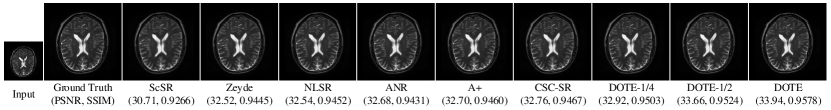

MRI Super-Resolution. As we introduced in Section 1, we first address image SR as one of cross-modality image synthesis. In this scenario, we investigate the T2-w images of the IXI dataset for evaluating and comparing DOTE with ScSR [1], A+ [2], NLSR [4], Zeyde [5], ANR [10], and CSC-SR [9]. Generally, LR images are generated by down-sampling HR ground-truth images using bicubic interpolation. We perform image SR with scaling factor 2, and show visual results in Fig. 2. The quantitative results are reported in Fig. 3, while the average PSNRs and SSIMs for all 144 test subjects are shown in Table 1. The proposed model achieves the best PSNRs and SSIMs. Moreover, to validate our argument that DL-based self-optimization strategy is beneficial and requires less training data, we compare DOTEnodualsubscriptDOTEnodual\textrm{DOTE}_{\textrm{nodual}} (removing dual mapping term) and DOTE under different training data size (i.e., 14,12,34141234\frac{1}{4},\frac{1}{2},\frac{3}{4} of the original dataset). The results are listed in Table 2. From Table 2, we see that DOTE is always better than DOTEnodualsubscriptDOTEnodual\textrm{DOTE}_{\textrm{nodual}} especially with few training samples.

Refer to caption

Figure 2: Example SR results and the corresponding PSNRs and SSIMs.